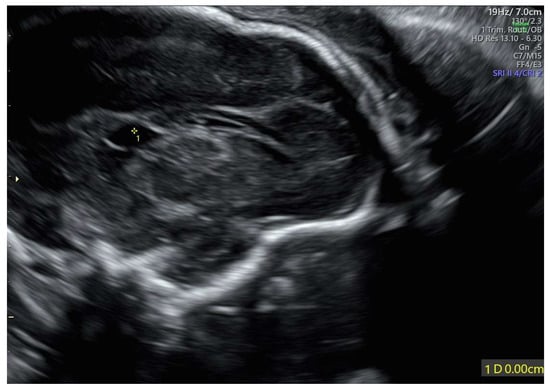

The velum interpositum cyst was located posteriorly to the corpus callosum (Figure 2).

Figure 2.

Velum interpositum cyst: the structure (indicated by 1*) was located posteriorly to the corpus callosum.

In our case, the US findings, at 21 weeks + 3 days, included IUGR, oligo/anhydramnios, velum interpositum cyst, and mild pericardial effusion. Despite oligo/anhydramnios, both kidneys were not hypoplastic, measuring in longitudinal diameter 19.3 mm on the left, and 20.5 mm on the right, respectively [12].